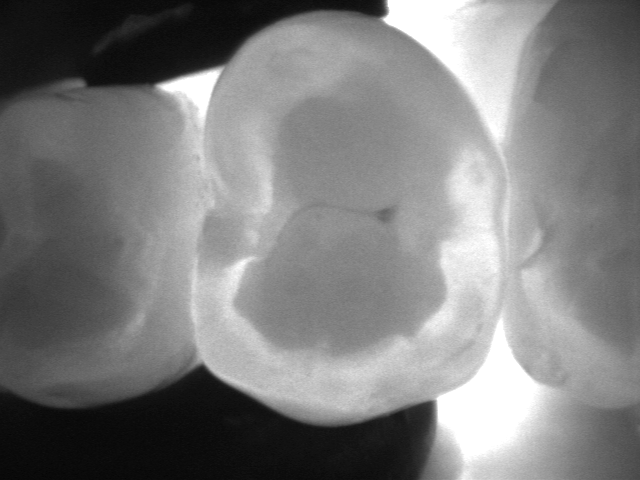

La videocamera digitale sulla testa del manipolo rileva luci ed ombre all’interno del dente e proietta l’immagine ottenuta sullo schermo del pc in tempo reale: le parti sane, che consentono il passaggio della luce, risultano chiare, quelle lesionate, che al contrario lo bloccano, si distinguono nettamente come aree scure.

Le immagini in bianco e nero, altamente dettagliate, ricordano molto le radiografie ma di fatto sono state del tutto ottenute senza radiazioni, soltanto per transilluminazione laser!

Vedere l’estensione della lesione, se ancora soltanto sullo smalto o già sconfinata in dentina, e la sua esatta posizione sono informazioni fondamentali per impostare una terapia che sia il più possibile conservativa.

I fermo immagine ottenuti servono a motivare il paziente e rendere più comprensibile il piano di trattamento. Nel caso di lesioni iniziali permettono, inoltre, un attento monitoraggio nel tempo, ad ogni successivo controllo.

Consente la diagnosi precoce di cracks (incrinature, fratture), demineralizzazioni e carie (occlusale, prossimale o secondaria sotto vecchi restauri), quando sono sopragengivali.

Evidenzia la carie con più sensibilità e attendibilità della sola ispezione visiva e molto prima che appaia alle radiografie, rendendo possibili trattamenti profilattici o minimamente invasivi.